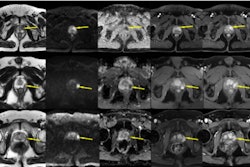

PI-RADS incorporates rules by which ancillary findings can upgrade a dominant score to a higher final category, the group noted. But evidence as to how this type of upgrade impacts various pathways for diagnosing prostate cancer is unclear. To address the knowledge gap, the team evaluated the benefit of using PI-RADS upgrading rules with MRI-directed diagnostic sequences.

Correia and colleagues conducted research that included 716 patients without known prostate cancer who underwent prostate MRI followed by biopsy between January 2016 and May 2020. The investigators defined clinically significant prostate cancer as being in a grade group equal to or greater than 2, and they compared the detection of disease between dominant (that is, no upgrade rule applied) and upgraded lesions.

The authors reported no significant differences for diagnosis of clinically significant prostate cancer between dominant and upgraded PI-RADS 3 transition zone lesions (20% compared with 19%), PI-RADS 4 transition zone lesions (33% compared with 26%), or PI-RADS 4 peripheral zone lesions (58% compared with 45%). They also found the following: